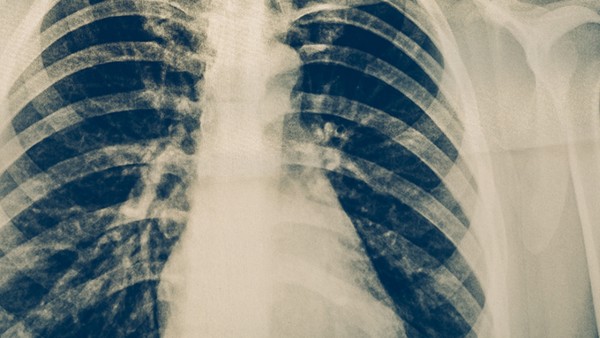

1.病情好转:肺结核是由结核杆菌感染引起的慢性传染病,主要通过呼吸道传播。临床上以咳嗽、咳痰、咯血等为主要症状。如果患者的病情比较轻,而且身体抵抗力比较好,在医生的指导下规范用药治疗,一般在2-3个月内就可以达到临床治愈的效果;